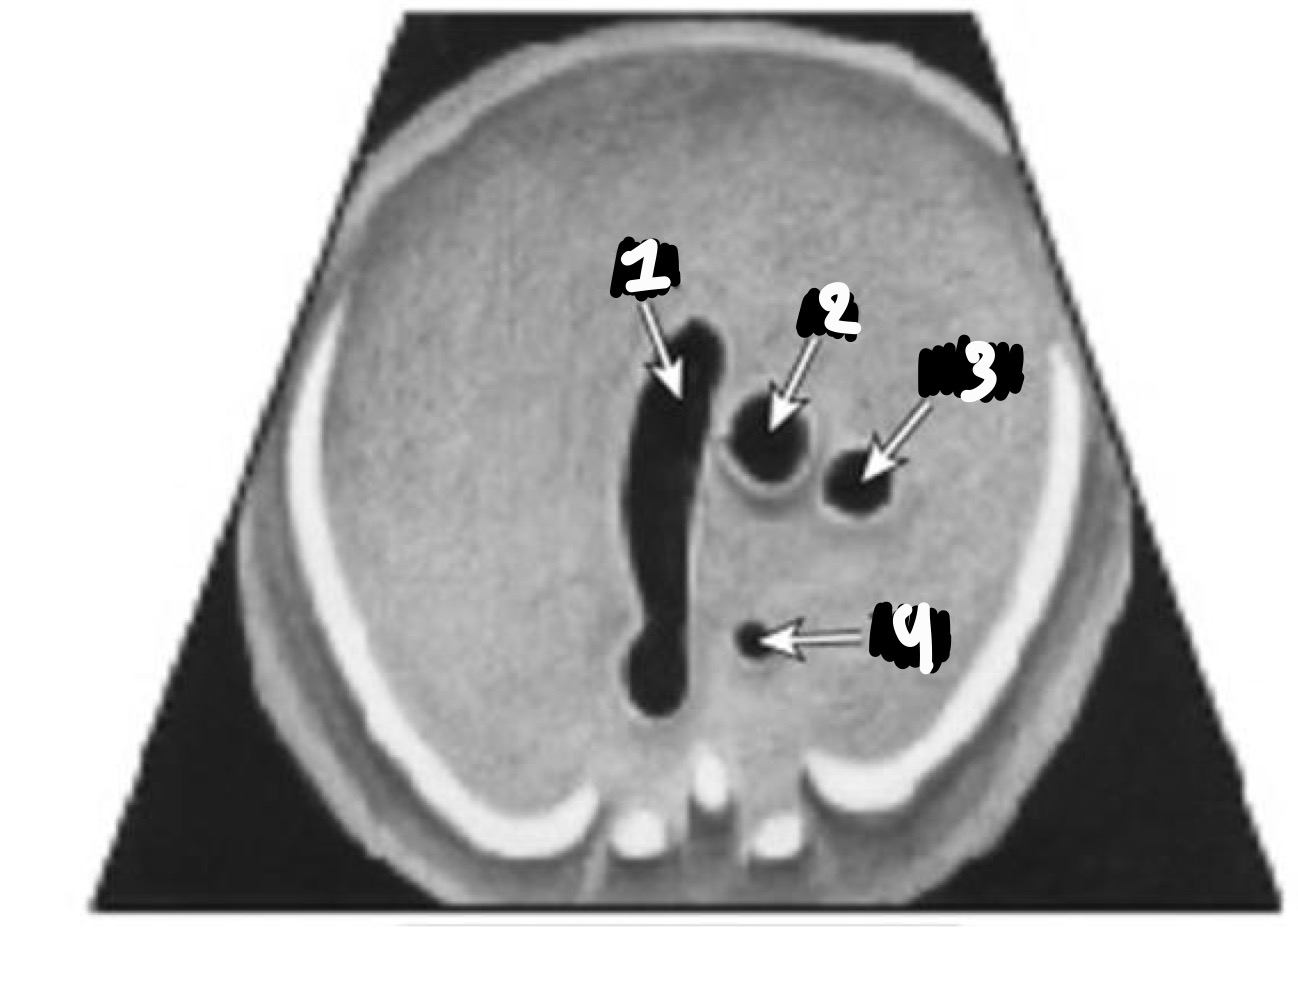

What 4 chamber views are these from left to right?

Apical

Subcostal

Basal

What are the three angles used to obtain the 4-chamber view

Apical, subcostal, basal

What should be seen on either side of the chest in a proper view

Ribs

What should the cardiac axis be

~45° to the left

What should be true about the interventricular septum

It should be intact

How should the atria and ventricles appear

Symmetric

Which valve is more apical, tricuspid or mitral

Tricuspid

Where should the inferior pulmonary veins enter

Left atrium

Where is the aorta located relative to the left atrium

Posterior

What structure is seen in the right ventricle

Moderator band

Where does the foramen ovale flap open

Into the left atrium